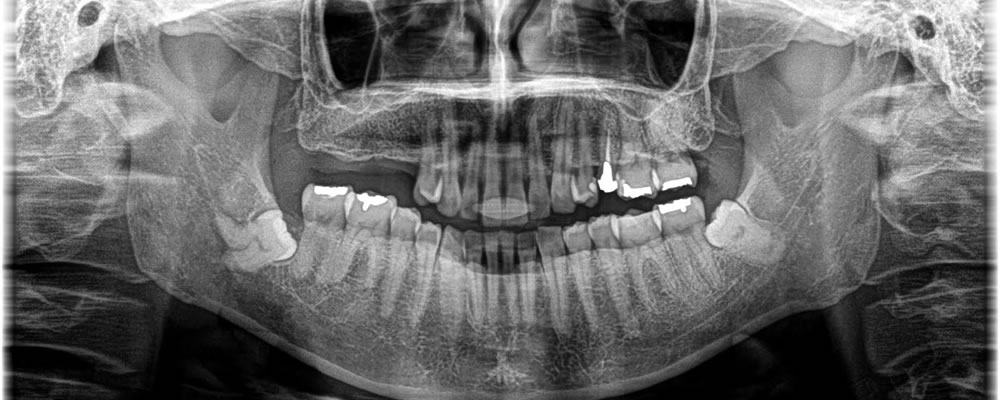

マウスピース矯正(インビザライン)で前歯の叢生を改善した症例

年齢

30代

性別

男性

症例を見る